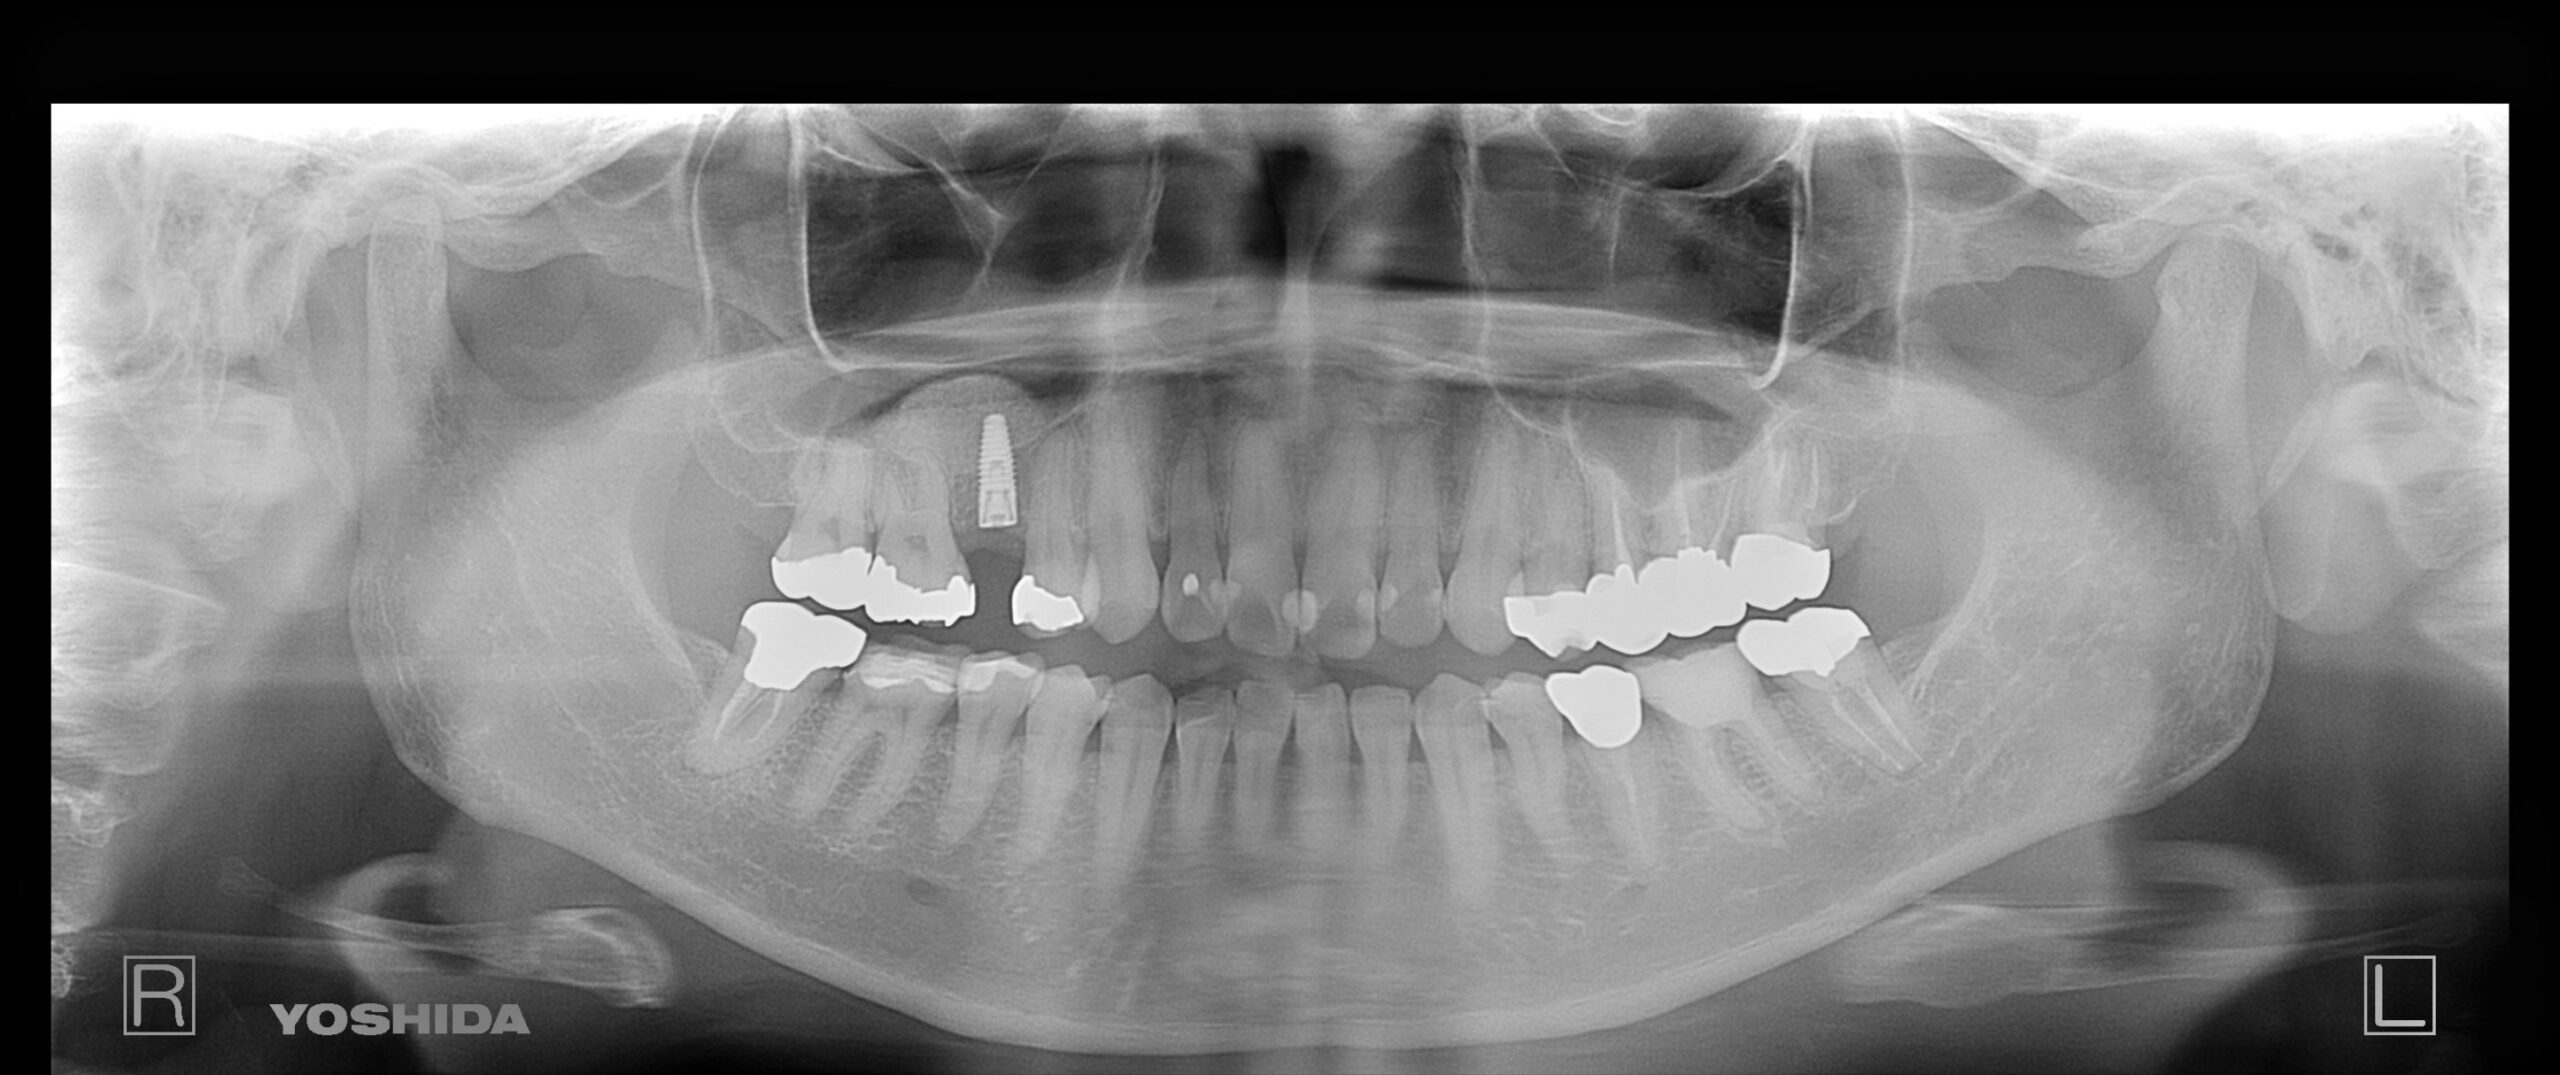

右下奥歯のインプラント症例

Before

• 右下6番欠損です。

• インプラントを埋入するのと同時にヒーリングキャップを取り付けました。

After

治療内容

右下の奥歯を根の先の膿が原因で抜歯された患者様です。

ブリッジ治療では両隣の歯を大きく削らないといけない為、インプラント治療を希望されました。

骨の治り方が歪で、頬側の骨が大きく足りないため骨造成を行い、インプラントを埋入した日にヒーリングキャップを装着し、インプラントが骨と結合するまで待ちます。

その後、型取りをし被せ物をスクリューにて装着しています。

担当歯科医師:平沼 佳朗

治療期間・回数

約10か月

費用

骨造成込み ¥616,000

リスク・副作用

術後に痛みや腫れ、出血を伴います。

口腔内の清掃不良によりインプラントの歯周病(インプラント周囲炎)になる可能性があります。定期的なメインテナンスが必要です。